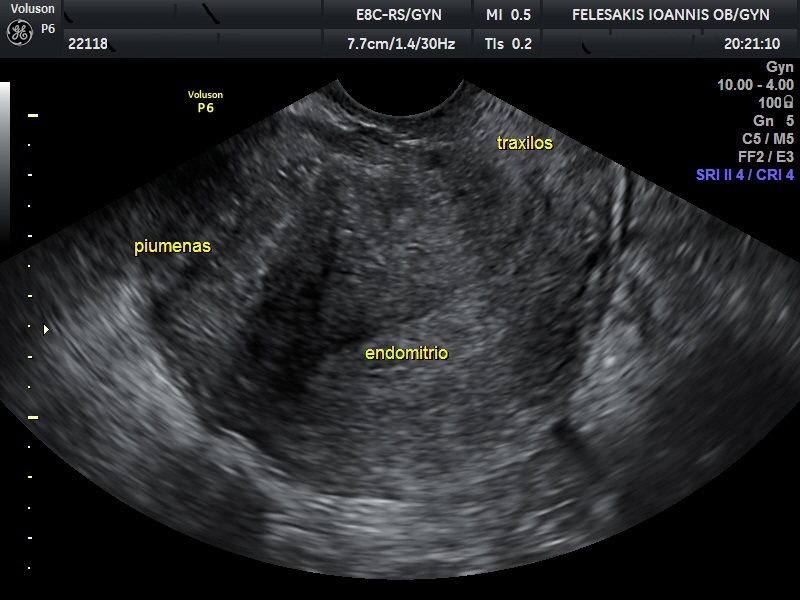

Τα συνηθέστερα συμπτώματα των γυναικών είναι η δυσμηνόρροια, η μηνορραγία και ο πόνος κατά την επαφή (δυσπαρεύνια). Σημαντικό είναι να τονιστεί, ότι η αδενομύωση δεν οδηγείται σε εξαλλαγή σε καρκίνο. Η διάγνωση της αδενομύωσης είναι δύσκολη, καθώς η υπερηχογραφική της εικόνα, πολλές φορές ομοιάζει με αυτή των ινομυωμάτων. Τη λύση έχει δώσει η Μαγνητική Τομογραφία (MRI) η οποία και βοηθάει στη διαφορική διάγνωση της υποκείμενης πάθησης.